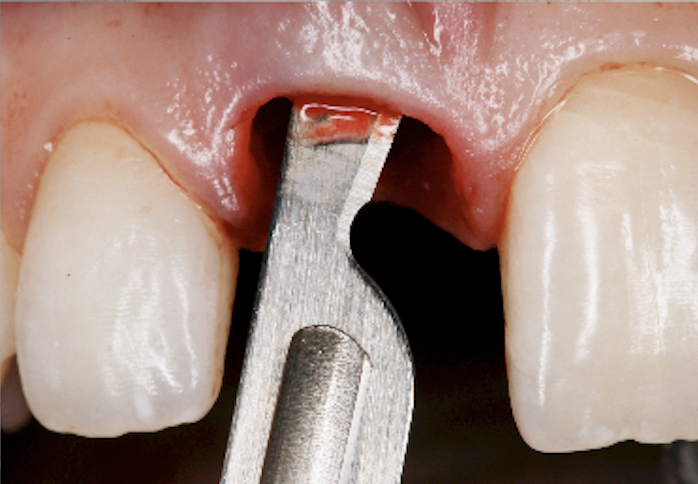

Gauze is placed over the extraction site to help control bleeding and assist in the formation of a blood clot.

We may need to stitch the incision to promote proper healing. Some stitches dissolve over time, while others require a follow-up visit for removal.